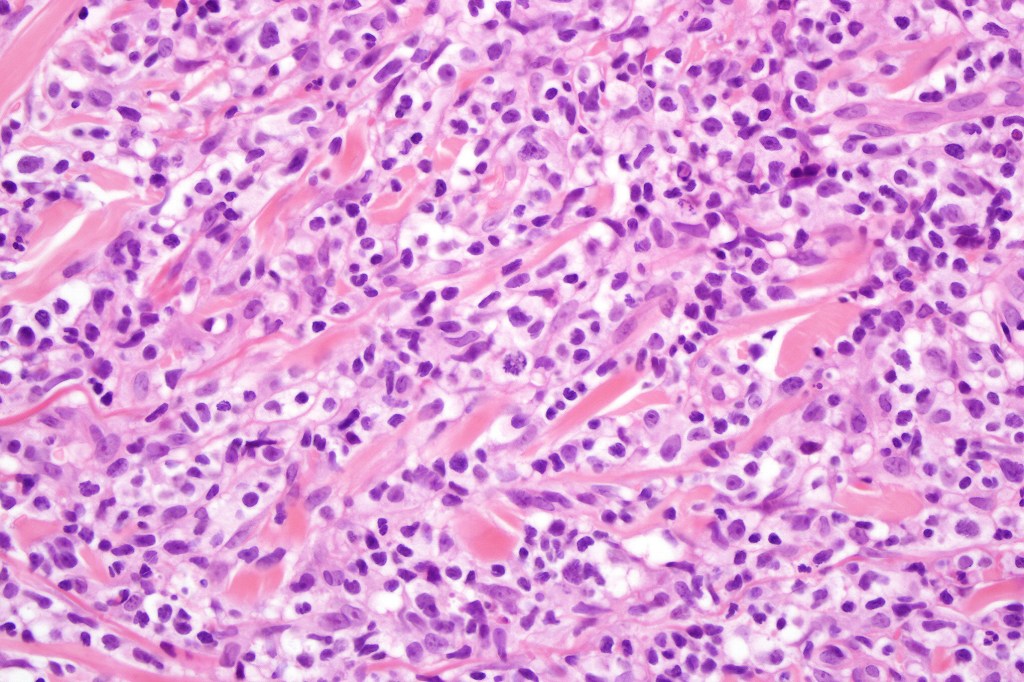

Histological features

The histological hallmark of mycosis fungoides is the presence of large atypical lymphocytes with a convoluted/cerebriform nuclear border (Sézary cells). These may be found at the epidermal-dermal jnuction and as collections within the epidermis (Pautrier microabscess). These are most easily found in plaque stage disease. The epidermal component can be subtle in patch stage disease and is often lost in tumor stage dsease. The classification into patch, plaque & tumor stage disease is less helpful histologically as the features merge from one to the other. It is all a matter of degree.

Tumor Stage Disease

•Epidermotropism is often minimal or absent

•Dense, broad diffuse or nodular, dermal infiltrate often extending into the subcutaneous fat

•Abundant Sézary cells. Frequently accompanied by very pleomorphic forms

•Mitoses often abundant, frequently abnormal

•CD30 expression correlates with transformation (cells X4 size of small lymphocytes comprising 25% or more of the infiltrate or the presence of a distinct large nodule)